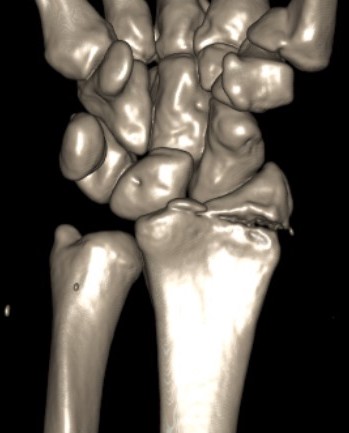

CT

Radial styloid + dorsal rim fractures